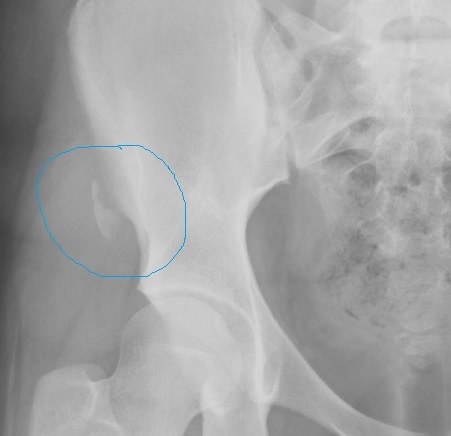

Identify

avuslion fracture